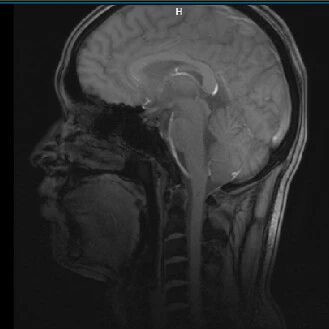

“脑脊液弦音,破译瘤境秘章”——脑脊液细胞因子检测解锁中枢神经系统弥漫大B细胞淋巴瘤案例分享

“脑脊液中藏星斗,细胞因子破双炎”——脑脊液细胞因子在病毒性脑炎合并难治性结核性脑膜炎诊治中的作用

中枢神经系统特殊菌感染的诊疗思考